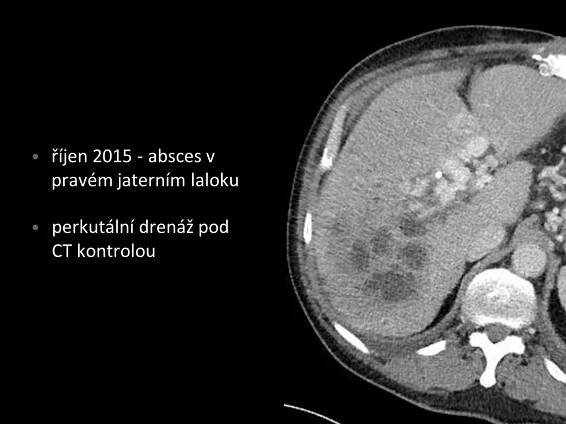

Cholestáza je definována jako porucha tvorby žluči v játrech nebo jejího toku, která může nastat kdekoliv mezi sinusoidální membránou hepatocytu a Vaterskou papilou.

Cholestáza znamená poruchu odtoku žluči a příznaky s tímto stavem spojené. Cholestáza může vzniknout na podkladě patologie nacházející se v játrech (intrahepatální cholestáza) i mimo jaterní tkáň (extrahepatální cholestáza).